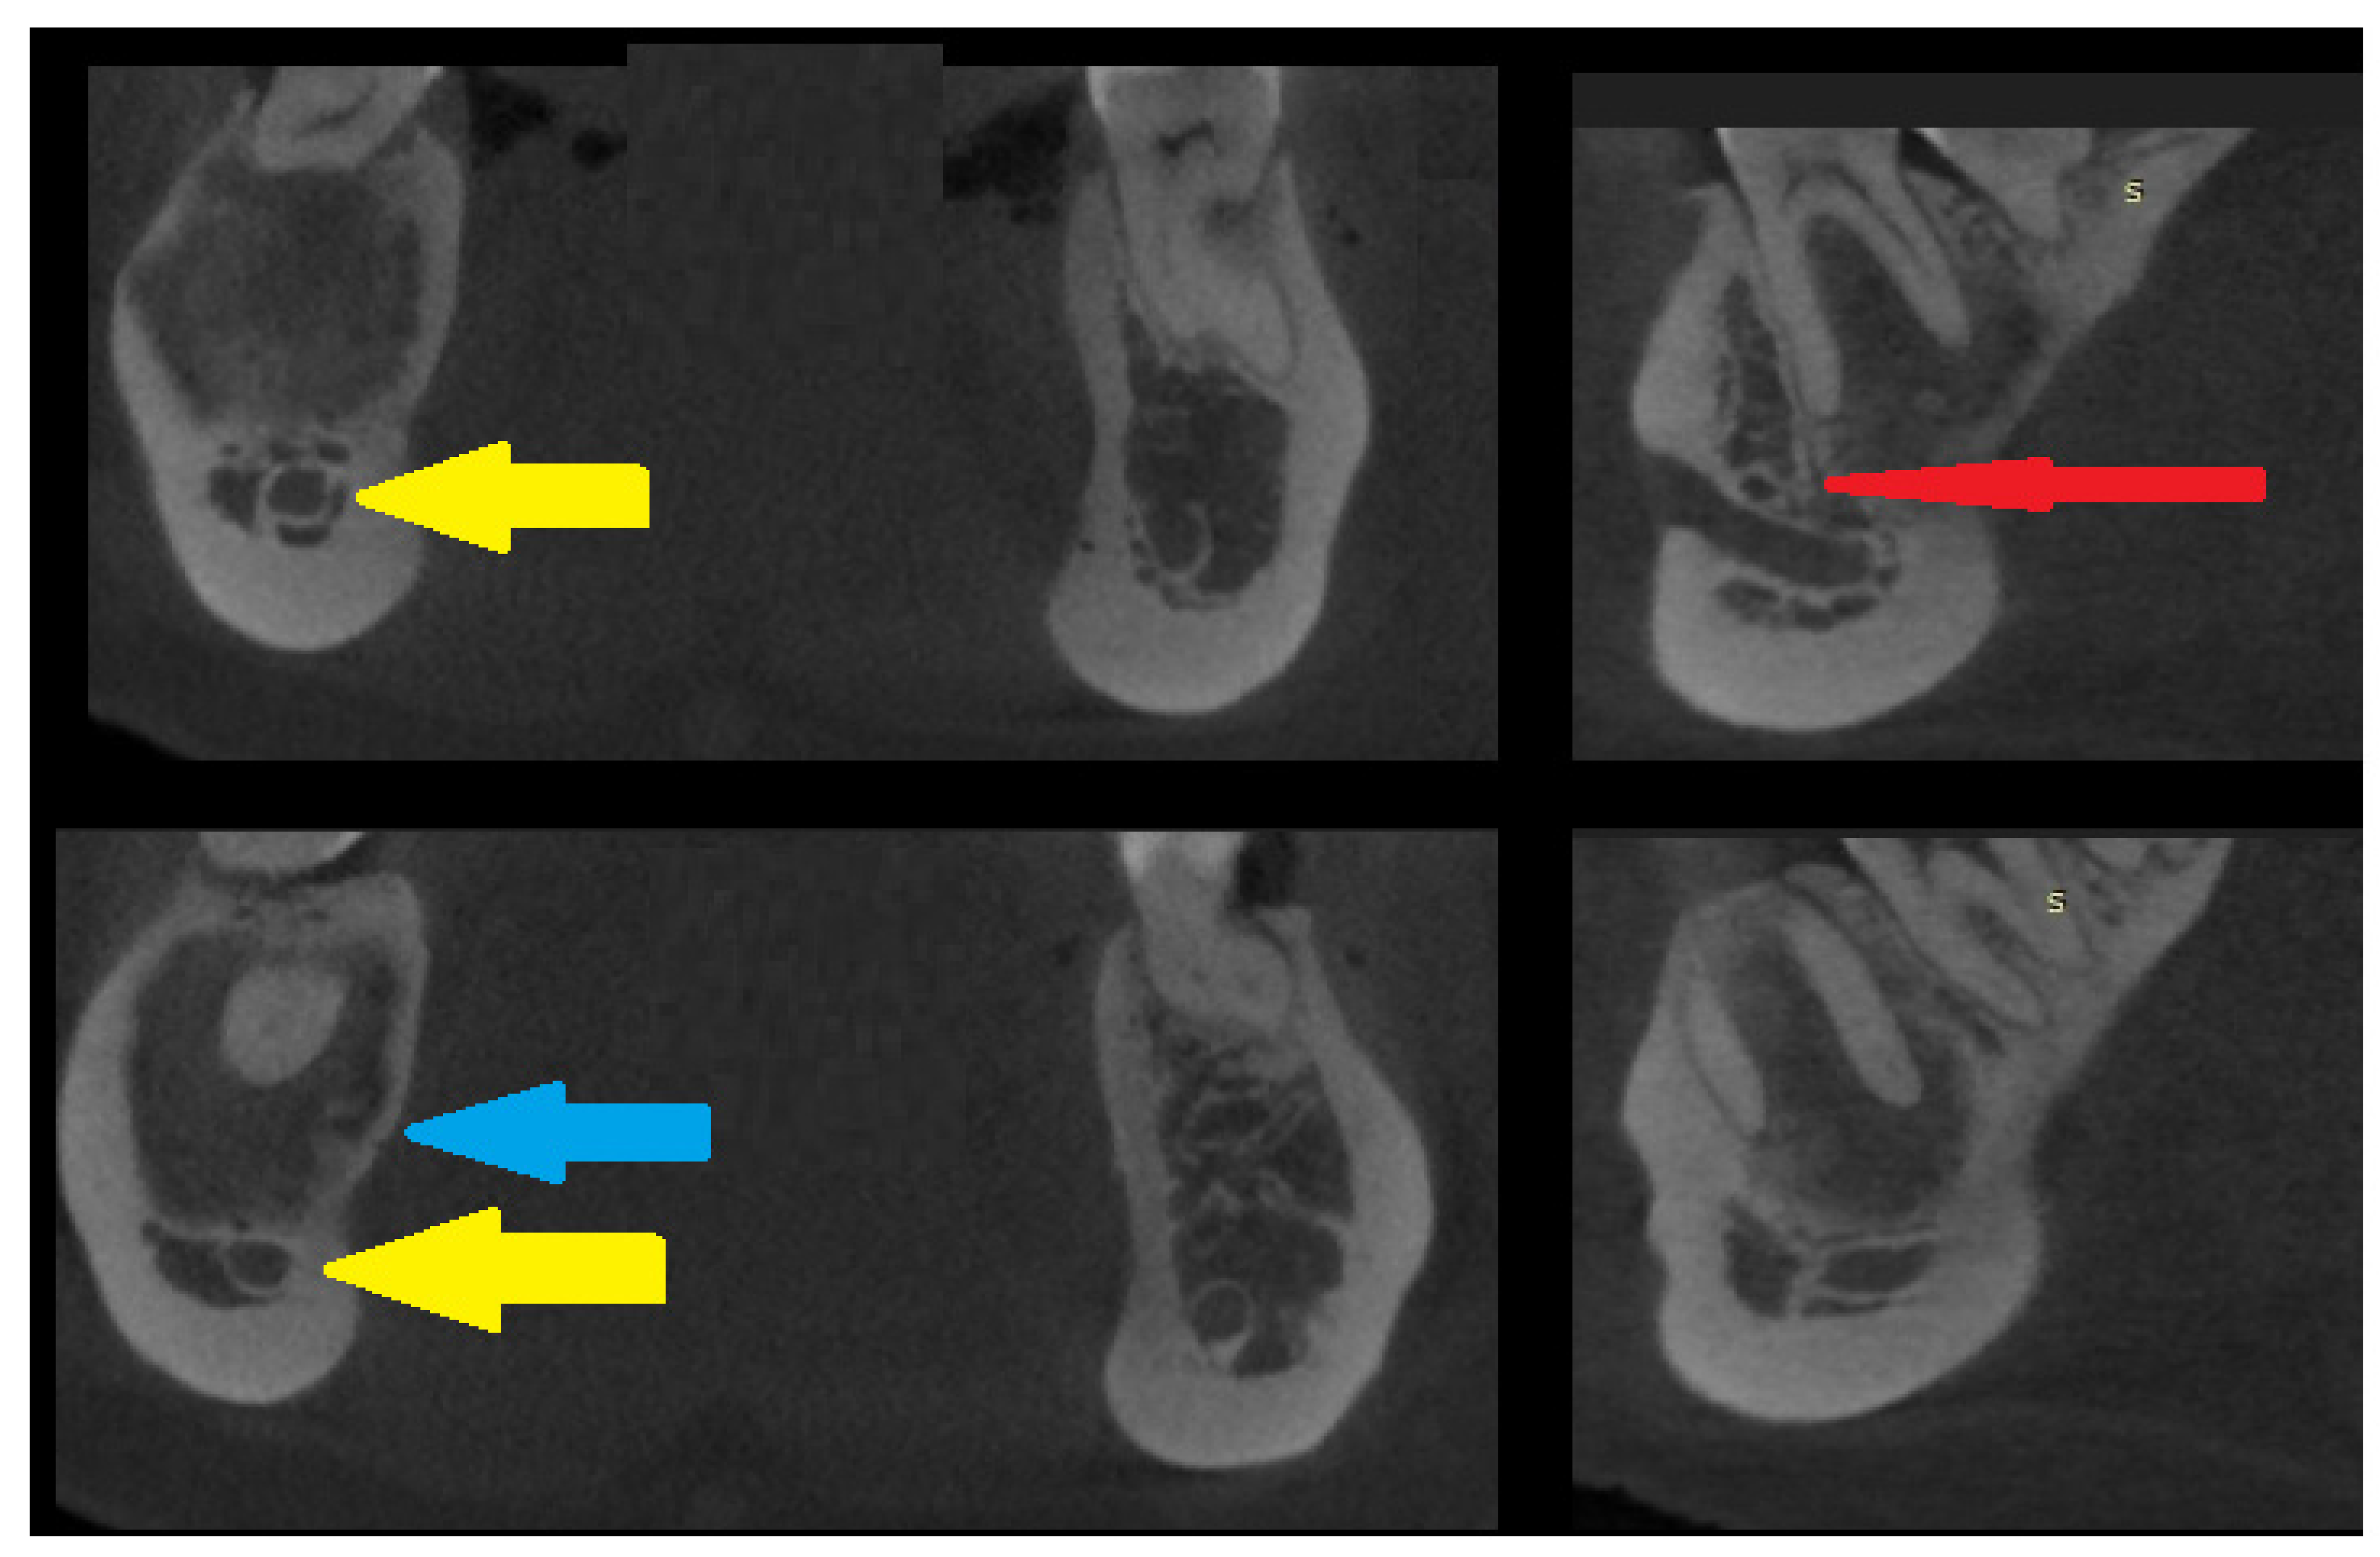

Figure 3. CBCT scans in the coronal and sagittal views—slight bone swelling with cortical thinning (blue arrow) and a non-displaced mandibular canal (yellow arrow). A clear root structure without any erosion, resorptions, or other pathology is visible. The red arrow on the sagittal scan reveals a good condition of the nerve and blood vessels entering the periapical area of the first right molar tooth in the mandible. This cloud-like appearance is characteristic of many lesions in radiologic studies [1,2,3,4,5]. No extracortical bone spread is visible. Identifying the extent of lesion calcification or the occurrences of bone- or tooth-like structures within the cavity could improve diagnostic accuracy. A study conducted by Gennaro et al. confirmed that diagnosis is challenging, but the main goal should always be predicting the right outcome for the patient. Each lesion in the jaw bones requires careful evaluation of the cortical bone, potential calcifications, presence of tooth-like structures, the status of the periosteum, and the formation of any new bones. On the other hand, a study by Merva Soluk-Tekkesin et al. indicated that the most common radiological feature found in their study was a mixed radiolucent/radiopaque internal structure [4]. The cloud-like radiological appearance made it very hard to distinguish between types of bone and fibro-osseous lesions and to determine the most suitable approach. This case underlines how CBCT and biopsy might, in some cases, influence the selection of a proper surgical approach. Many radiological scans of known bone lesions exhibit typical characteristics for each lesion. In this case, radiological differentiation of the lesion was very challenging, especially on PANX and CBCT. This OSF has two different radiological appearances and unclear borders. Quite often, only thorough histopathological evaluation can accurately reveal the different patterns of bone growth, maturation, and calcification that confirm the diagnosis of OsF. Abbreviation—S: surgery side (right).